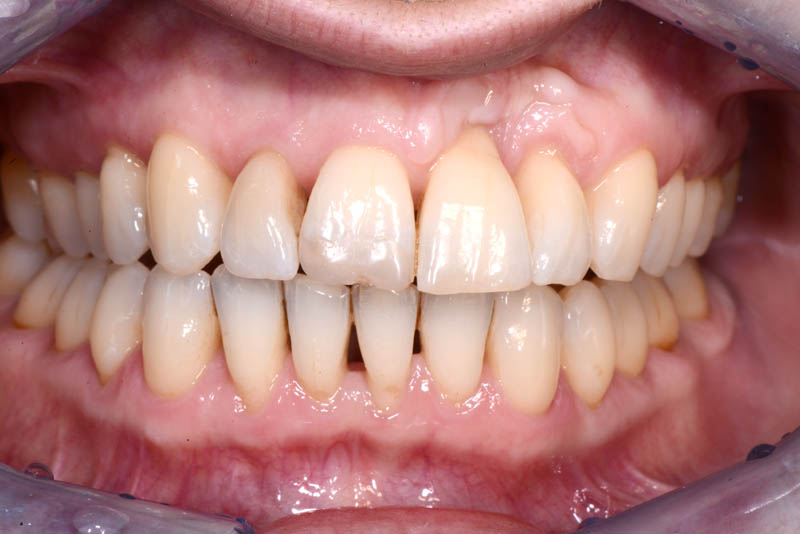

The healing has now reached a 5-year follow-up.

The patient is absolutely delighted with the outcome, but I have repeatedly (and unsuccessfully) encouraged her to undergo a small additional graft to address the minor residual recession on tooth 21.

5 years Follow up